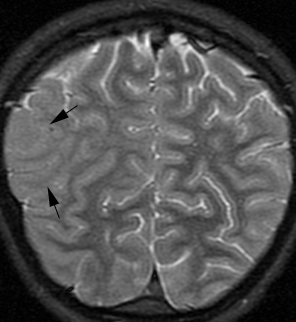

麻疹包涵体脑炎 (MIBE) 是免疫功能低下个体麻疹感染的一种罕见表现,通常在麻疹感染后 1 年内出现。疾病起病为亚急性,进行性神经功能障碍在数周至数月内发生。亚急性硬化性全脑炎 (SSPE) 是一种罕见的退行性中枢神经系统疾病,其特征是行为和智力恶化以及癫痫发作,通常发生在野生型麻疹病毒感染后 7 至 11 年。2 岁之前感染的儿童感染率最高。